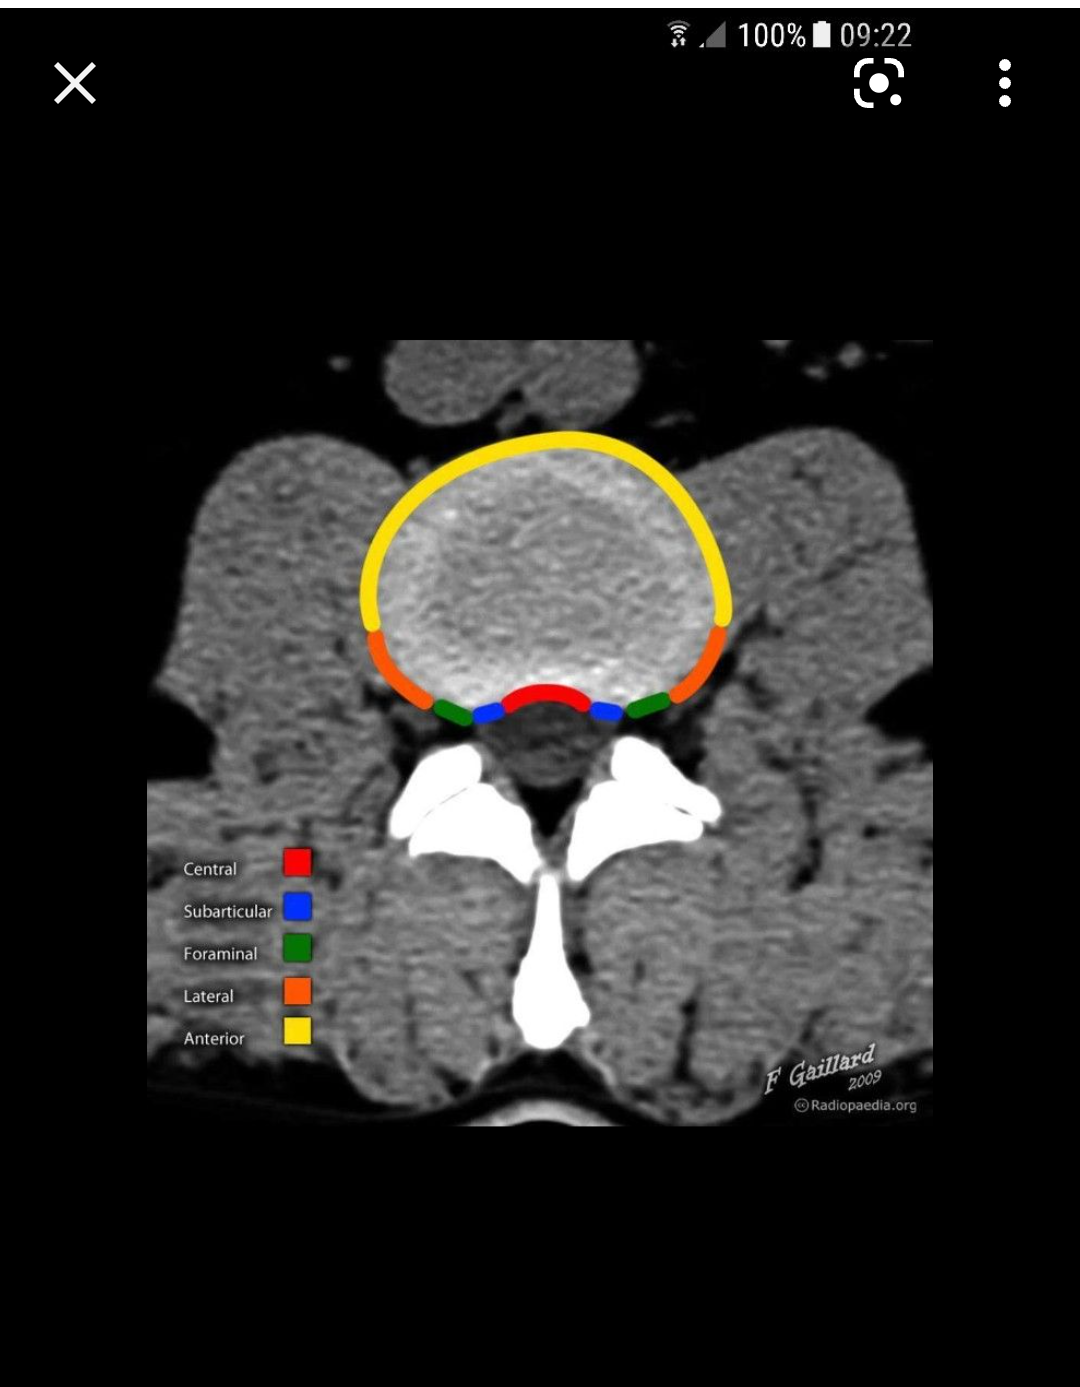

Лечението на дискова херния може да бъде консервативно или хирургично. В консервативното лечение се използват нестероидни противовъзпалителни лекарства, аналгетици, физиотерапия, балнеолечение, ЛФК и други. Хирургичното лечение се налага в случаи на тежки увреждания или когато консервативните методи не доведат до подобрение. Алтернативните лечебни методи за дискова херния включват остеопатия, боуен терапия, хомеопатия, озонна нуклеолиза и други алтернативни терапии, които се различават от традиционните медицински подходи. Основните методи за лечение на дискова херния включват първична терапия с противовъзпалителни лекарства, почивка, подходящи упражнения, физиотерапия, кинезитерапия, ергономични столове и правилна стойка при седене. В някои случаи може да са необходими хирургични интервенции. Различните лечебни методи за дискова херния включват физиотерапия, масажи, балнеолечение и упражнения. Тези методи могат да се използват преди и след операция. Освен това е важно да се консултират с неврохирург и ортопед за персонализиран подход към лечението.